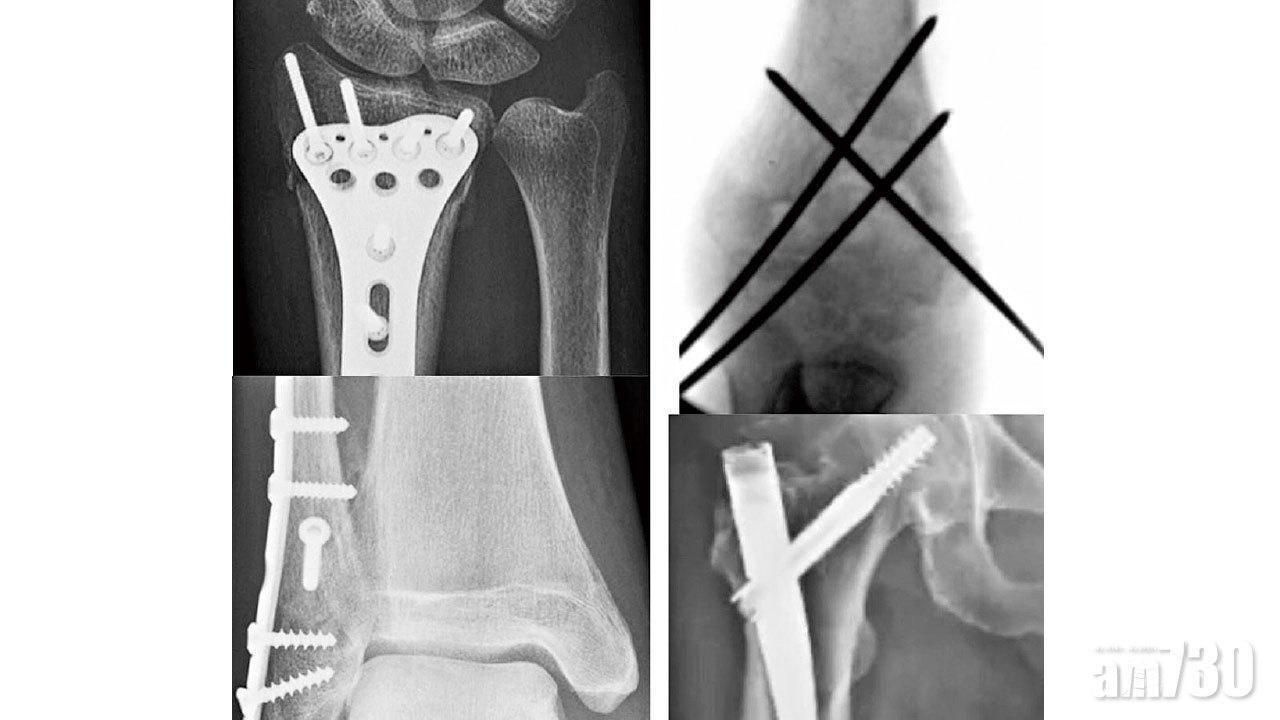

髓內釘穿過,股骨折斷得堅壯。前臂鋼板安裝妥當,和你互靠著,等你安康。

註釋:本文是黃偉文填詞、Dear Jane主唱的流行曲《銀河修理員》之二次創作。用於治療骨折的金屬植入物,主要由不銹鋼及鈦合金製成。常用的植入物包括:鋼針、螺絲、鋼片、髓內釘、鋼線和關節假體等。骨折手術可分為閉合式和開放式復位,以內固定術為主,並在特定情況下使用外固定支架或骨牽引。